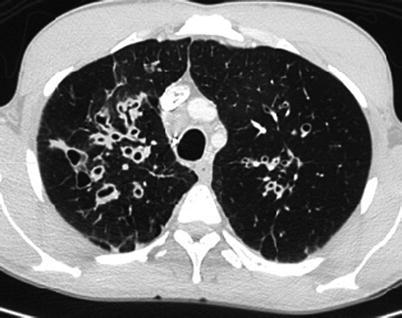

Postinfectious bronchiolitis obliterans (constrictive bronchiolitis or obliterative bronchiolitis) is a clinical syndrome of chronic airflow obstruction associated with inflammatory changes in the small airways as response to epithelial injury associated with infections. It is particularly associated with Adenovirus, RSV, Varicella, and severe Mycoplasma infection. The chest x-ray findings are often nonspecific and can appear normal, but the most common abnormality is hyperaeration (Yalcin et al. 2003). On HRCT, there is a mosaic perfusion pattern (Fig. 13.5). Perfusion is diminished in areas of parenchymal attenuation due to vasoconstriction secondary to hypoxia. Inspiratory and expiratory phases of ventilation are important in HRCT to better assess air trapping in this condition (Hansell et al. 1997). Peribronchial thickening, atelectasis, bronchiectasis, and sometimes lung volume reduction can also be seen. Swyer-James is a subtype of postinfectious bronchiolitis obliterans, which is typically unilateral. It can affect one lung segment, a lobe, or the entire lung. The characteristic chest radiographic and CT findings are hyperlucency due to the pulmonary hypoperfusion, reduction of vascular and hilar markings, and volume reduction of the affected lung or lobe (Daltro et al. 2011) (Fig. 13.6).

Fig. 13.5.

Postinfectious bronchiolitis obliterans. High-resolution CT scan images in expiratory phase demonstrate the typical “mosaic perfusion” pattern